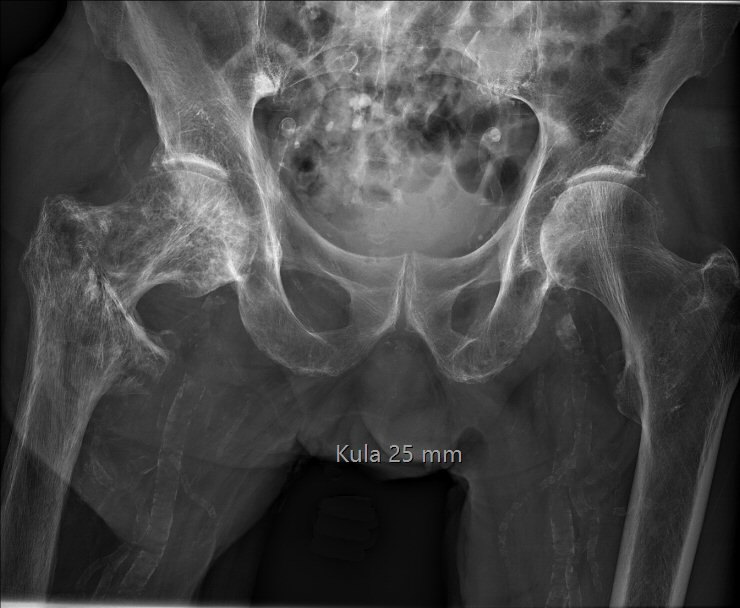

Röntgenundersökning som kan visa flera typiska tecken, t.ex. plötslig kaliberväxling av kortex, minskad skillnad mellan kortex och medulla, lateral böjning av femur eller anterior böjning av tibia.

Pagets sjukdom i höger femur, upptäcktes vid pertrokantär femurfraktur